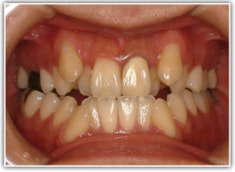

治療後(2年3ヶ月後)

骨格的な下顎前突の傾向は強くはありませんが、歯牙の状態によって反対咬合が認められます。LowTongue(低位舌)もあります。

歯根のパラレリング(平行性)が獲得されております。